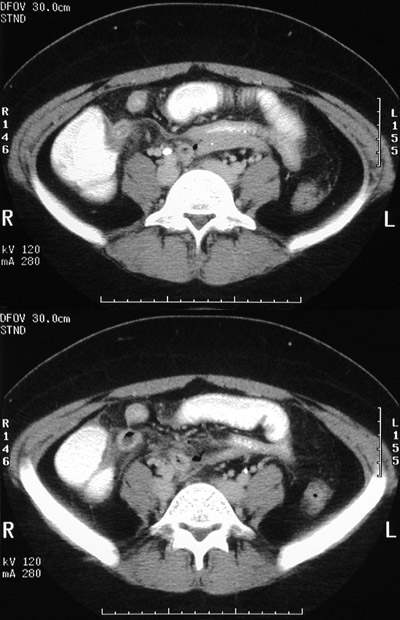

| Here is another example of acute appendicitis with dilation to 17 mm and wall thickening. This patient presented with a day-long history of lower abdominal pain. On physical examination, there was rebound tenderness in the right lower quadrant. The patient's WBC count was 13,900/microliter. |